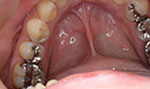

症例3(銀歯→白く)

20代の患者さんで金属が前から気になっているのでダイレクトボンディングで治したいと訴えておりました。

金属がなくなってすっきりし見た目も良くなって喜んでおられました。

回数2回 費用25000円

術前

術後